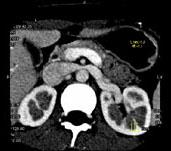

问题 女 ,24 岁,发作性肉眼血尿1 年,实验室检查:尿蛋白 (- +)、红细胞1 2/HP,尿蛋白直立试验 (+),CT扫描如图,下列说法正确的是 ( )

选项 A、左侧肠系膜上动脉与腹主动脉夹角增大 B、考虑为左肾静脉胡桃夹综合征 C、左肾静脉走行至肠系膜上动脉与腹主动脉间变细,近左肾处扩张 D、左侧肠系膜上动脉与腹主动脉夹角变小 E、双肾大小形态正常

答案 BCDE